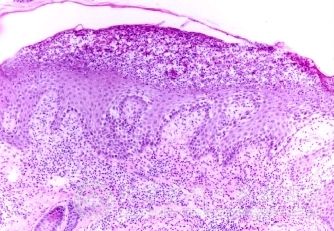

引起瘙痒性皮肤病的原因有什么?瘙痒性皮肤病是由各种原因引起的皮肤病,常常引起皮肤红、痒、等各种皮肤症状,为了避免瘙痒性皮肤病给我们工作生活带来的不良影响,一定要及时的进行瘙痒性皮肤病的治疗,从而使较好的瘙痒性皮肤病治疗结果。治疗瘙痒性皮肤病同时,也要知道引起瘙痒性皮肤病的原因。那么引起瘙痒性皮肤病的原因有什么呢?

4●某些皮肤病变,如银屑病、鱼鳞病等。